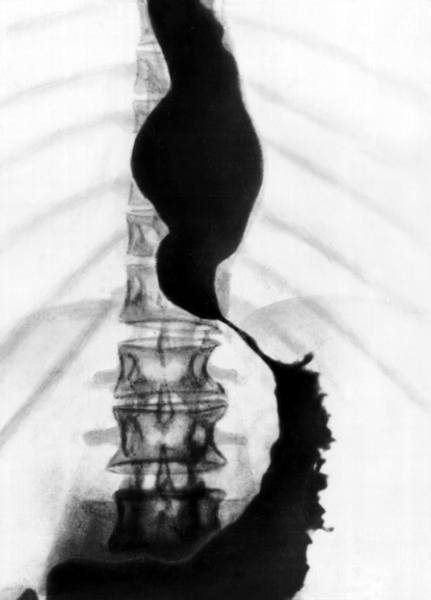

Ахалазия кардии при рентгенконтрастном исследовании